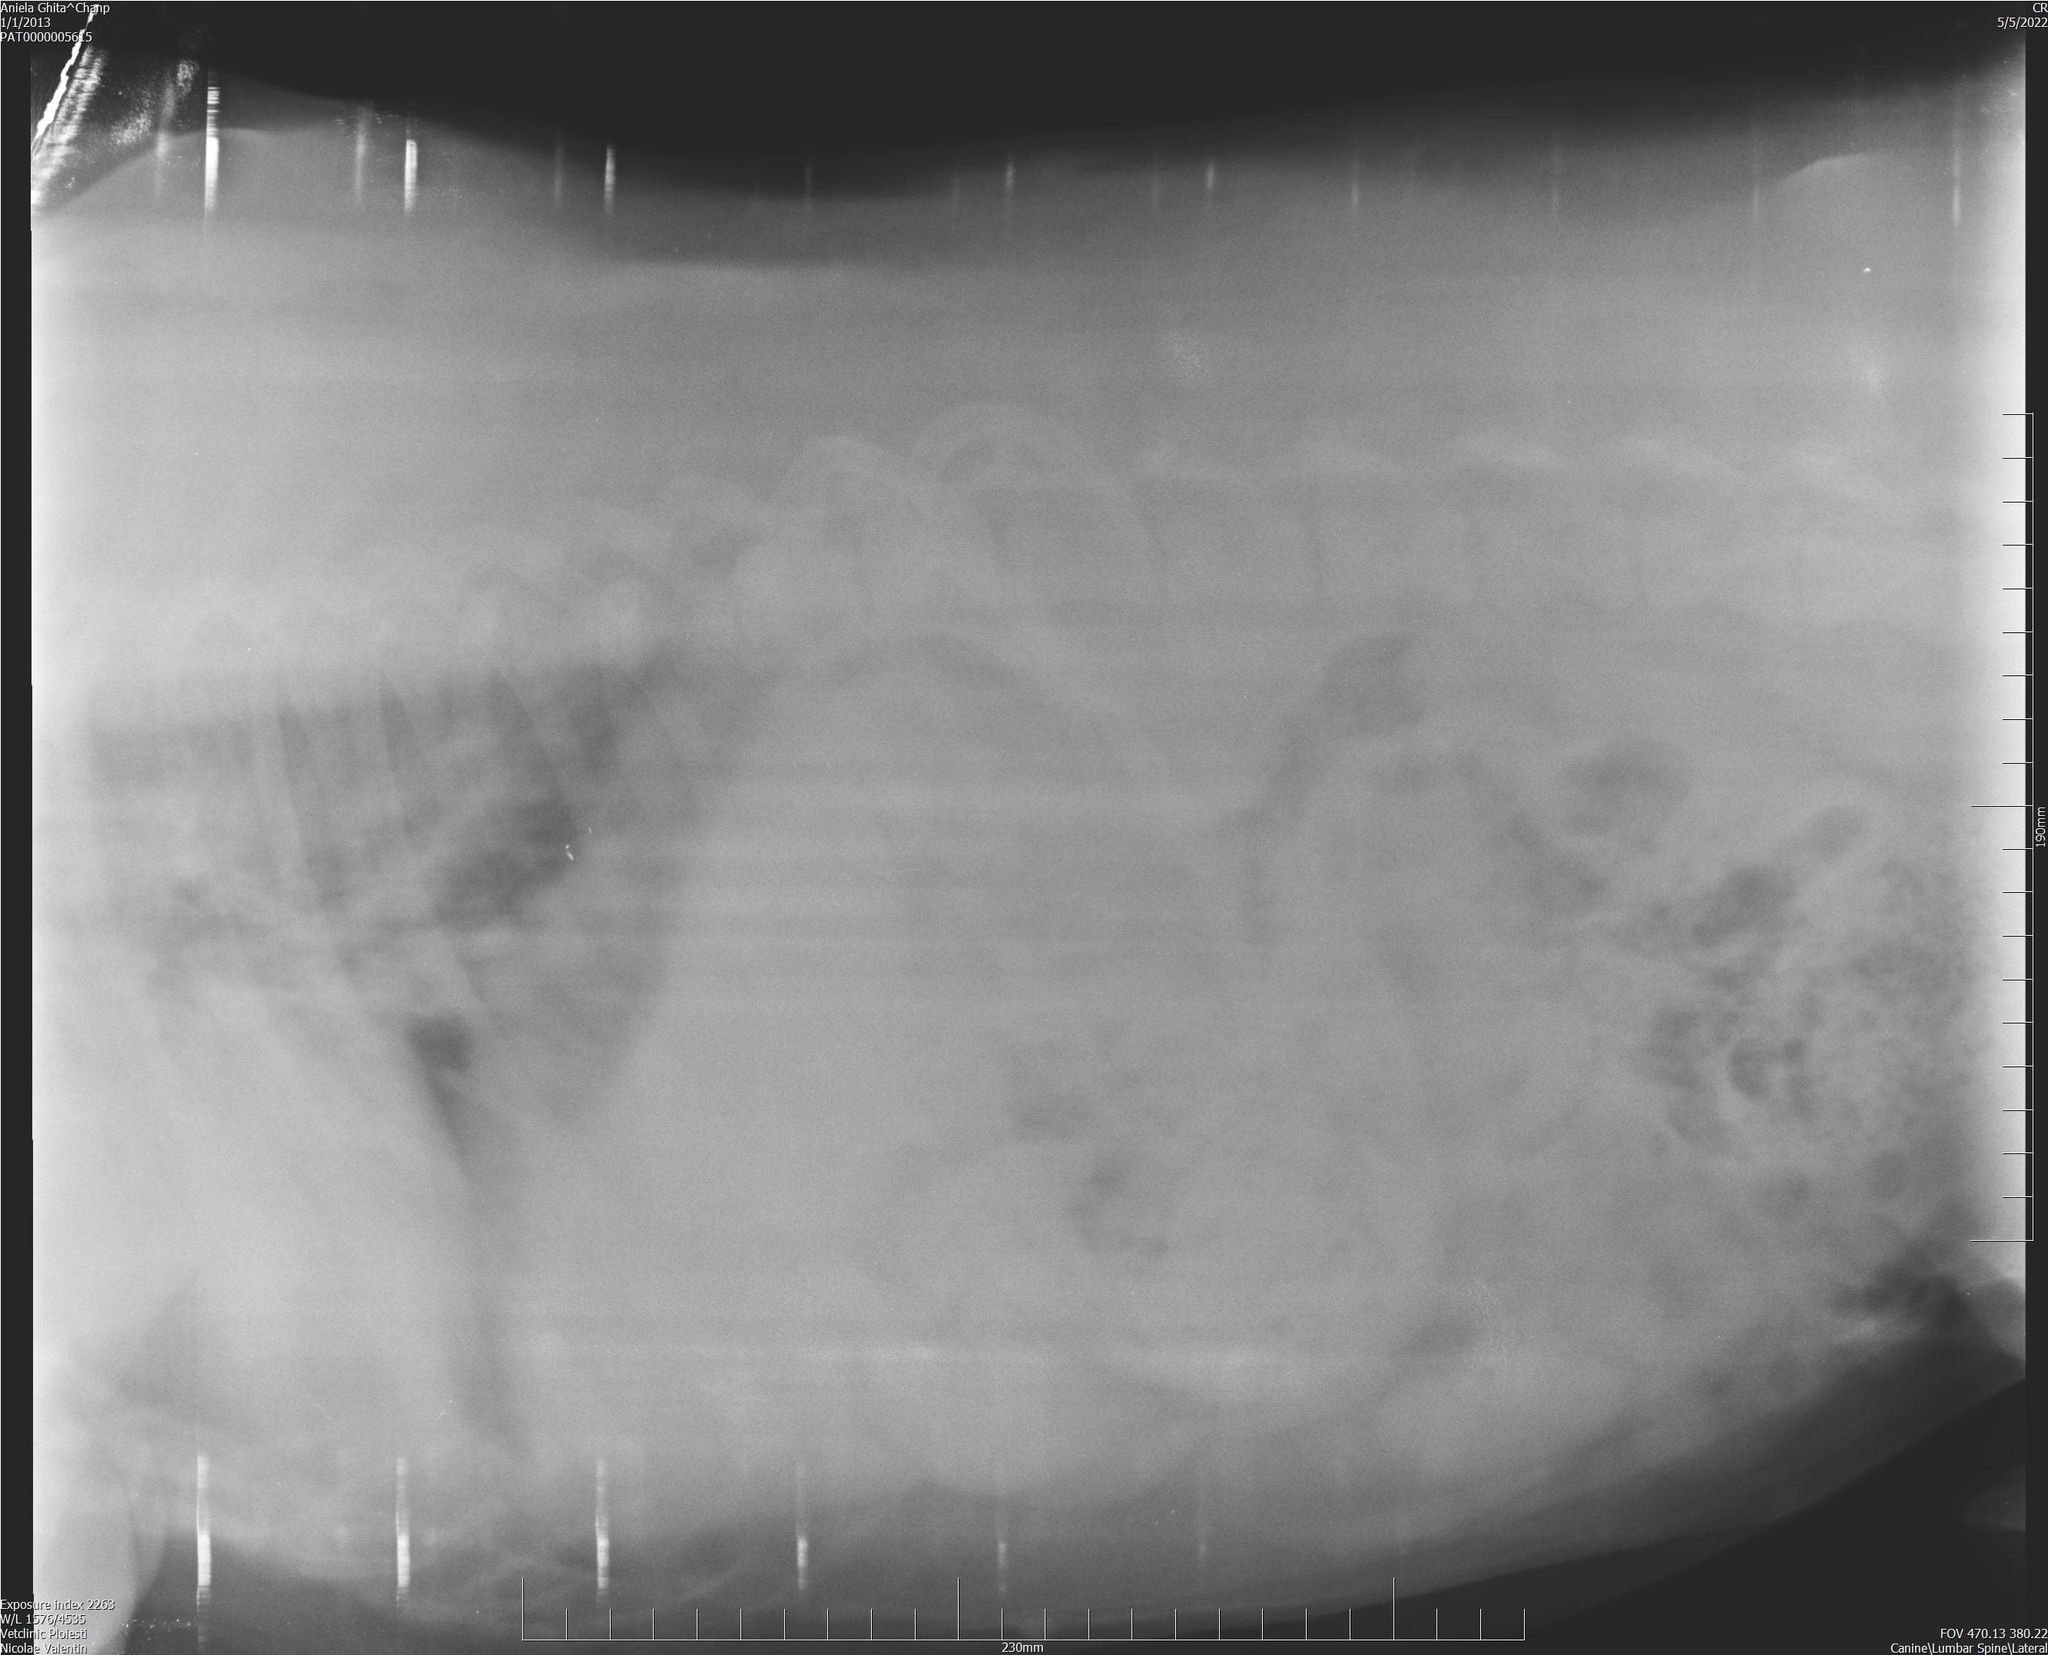

Befund Mai 2022: Degenerative Osteoarthritis der Femur-Tibia-Patella- und Hüftpfanne

| zur Besonderheit: | Degenerative Osteoarthritis der Femur-Tibia-Patella- und Hüftpfanne, schwere Beinfehlstellung hinten beidseitig, seit mind. September 2019 im Tierheim |

| zur Besonderheit: | Degenerative Osteoarthritis der Femur-Tibia-Patella- und Hüftpfanne, schwere Beinfehlstellung hinten beidseitig, seit mind. September 2019 im Tierheim |